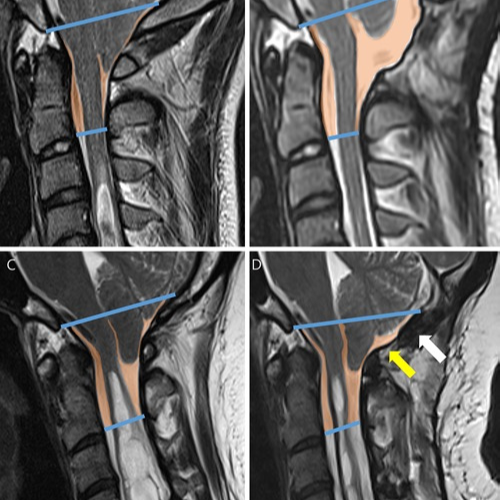

Mielopatía cervical

Compresión crónica de la médula espinal. Provoca alteraciones motoras, debilidad, pérdida de sensibilidad, problemas de coordinación, dolor cervical y afectación progresiva de la función neurológica.